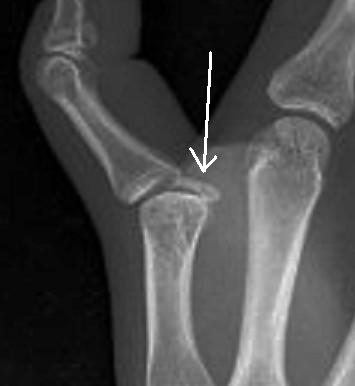

女性,25岁,半小时前坐公交车时手按压后第一掌指关节屈曲受限。

我认为是籽骨嵌入第一掌指关节。

正解:14楼,呵呵!那两粒是籽骨,其中一粒变异如薄饼样,按压伤后龛入掌指关节间隙。患者曾有类似发作史,几日后自行缓解。

哦,16楼才是正解。